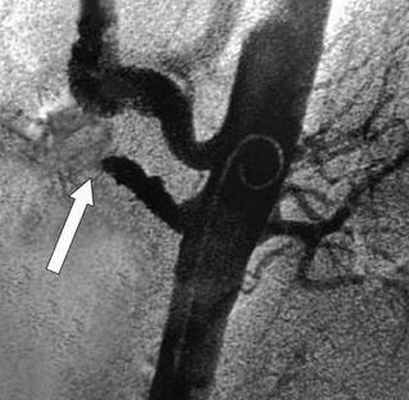

![Ангиография позволяет поставить точный диагноз и выполнить вмешательство по восстановлению кровообращения]()

Рентгеновская ангиография

Метода введения контрастного вещества непосредственно в интересующие артерии. Проводится через доступ к артериям на руке или на ноге. Позволяет прицельно изучить проходимость брыжеечных артерий и одновременно выполнить вмешательство по восстановлению проходимости закупоренной артерии. Ренгтеноангиография выступает диагностическим и лечебным методом одновременно. С помощью специальных катетеров и инструментов возможно проведение рассасывания тромбов (тромболизиса) или его удаления - тромбэктомии.